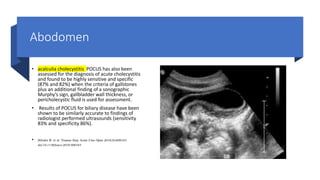

• acalculia cholecystitis POCUS has also been

assessed for the diagnosis of acute cholecystitis

and found to be highly sensitive and specific

(87% and 82%) when the criteria of gallstones

plus an additional finding of a sonographic

Murphy’s sign, gallbladder wall thickness, or

pericholecystic fluid is used for assessment.

• Results of POCUS for biliary disease have been

shown to be similarly accurate to findings of

radiologist performed ultrasounds (sensitivity

83% and specificity 86%).

• Hilsden R, et al. Trauma Surg Acute Care Open 2018;3:e000164.

doi:10.1136/tsaco-2018-000164